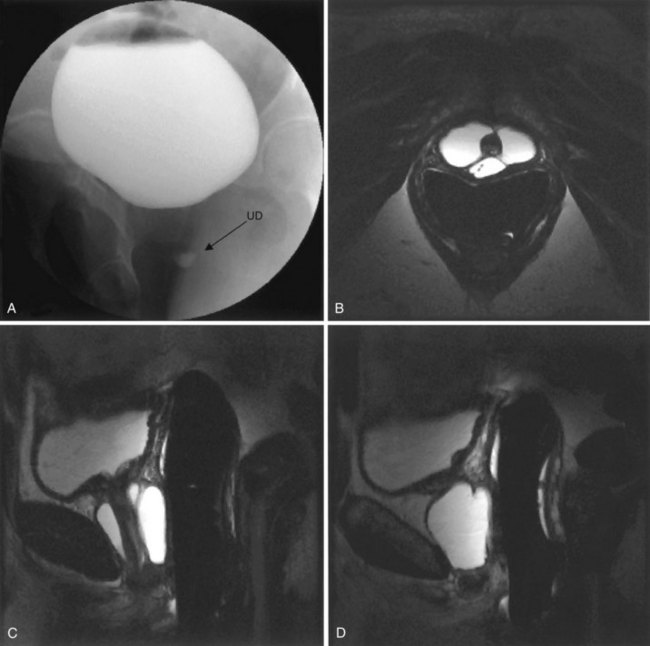

Figure 78–2 Voiding cystourethrogram (VCUG) demonstrating a bladder diverticulum in a male. A, The diverticulum is seen posterior to the bladder on this lateral voiding image (arrow points to urethra). There is a fluid-fluid level within the diverticulum representing the relatively denser contrast media settling below the urine. B, Later image from the VCUG demonstrates near emptying of the bladder with enlargement of the diverticulum.

As noted previously, bladder diverticula are often found incidentally in the radiographic investigation of recurrent urinary tract infections or other nonspecific lower urinary tract symptoms or signs. Fluoroscopically monitored voiding cystourethrography is an excellent study to detect bladder diverticula; however, false negatives are possible (Hernanz-Schulman and Lebowitz, 1985). A voiding urethrocystogram (VCUG) with anterior-posterior, oblique, and lateral images provides information regarding anatomy, location, and size and also associated vesicoureteric reflux and, importantly, emptying of the bladder diverticulum with voiding. Anomalous voiding into the diverticulum during a detrusor contraction may result in paradoxical enlargement of the bladder diverticulum during micturition (Wesselhoeft et al, 1963) (see Fig. 78–2). Presumably, this occurs as the contrast flows from an area of relatively high pressure in the bladder, during the detrusor contraction, to the diverticulum, which represents an area of low pressure. In some instances, the bladder may empty partly into the diverticulum and partly through the urethra. The amount of postvoid residual urine in the bladder diverticulum and bladder should be noted. Incomplete bladder emptying suggests that a urodynamic abnormality may be present, requiring further study.